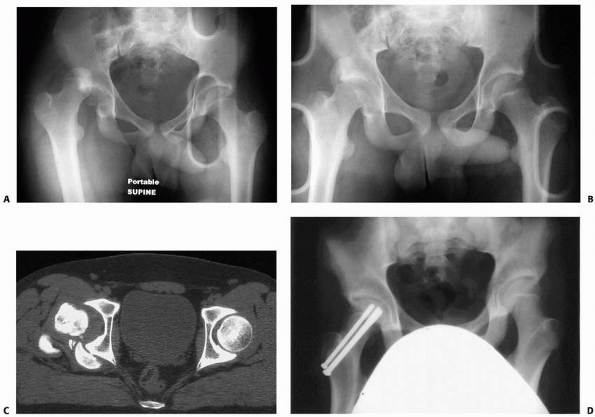

mechanism of injury often present with associated injuries. In one

study of 42 patients, there were 17 fractures in 9 patients and 1

closed head injury. Of the 17 fractures, 6 were posterior acetabular

wall factures and 1 required open reduction and internal fixation.66

Careful evaluation of this injury in younger children with MRI is

| FIGURE 21-22 A. A girl aged 13 years and 11 months sustained a left posterior hip dislocation in a motor vehicle accident. B. CT scan after reduction showed intra-articular bony fragments. C. At open reduction and capsulorrhaphy, the bony fragments were removed. Suture anchors were used to reattach capsule to bone. Ten months after injury, there is no sign of ON. Heterotopic ossification is seen. Bony fragments can also be removed arthroscopically. |

| FIGURE 21-24 A. A 12-year-old boy was tackled from behind in football. The right hip was dislocated. Reduction was easily achieved, but the hip was unstable posteriorly as a result of fracture of the posterior rim of the acetabulum. This is the most common accompanied fracture. B. The fracture and capsule were fixed via a posterior approach. C. Oblique view shows reconstitution of the posterior rim. |